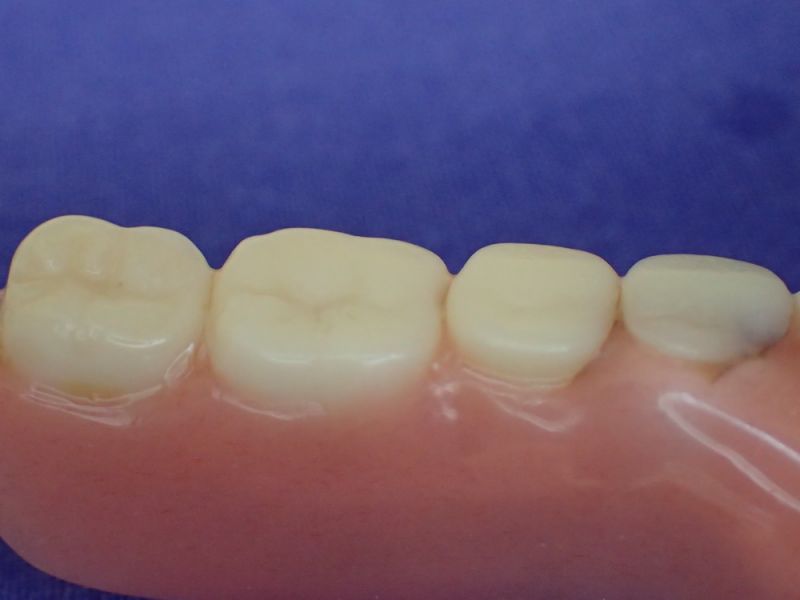

Nach inzwischen 12 jähriger Tragedauer wurden alle Kunststoffteile erneuert, das metallische Grundgeroüst der Arbeit erhalten und die Arbeit befindet sich in einem Zustand, der sich weitgehend an der Ersterstellung orientiert.

Bei derartigen Arbeiten ist es tatsächlich möglich grundlegende Konstruktionsmerkmale einer alten Arbeit zu übernehmen und Verschleißteile aus Kunststoff zu erneuern.